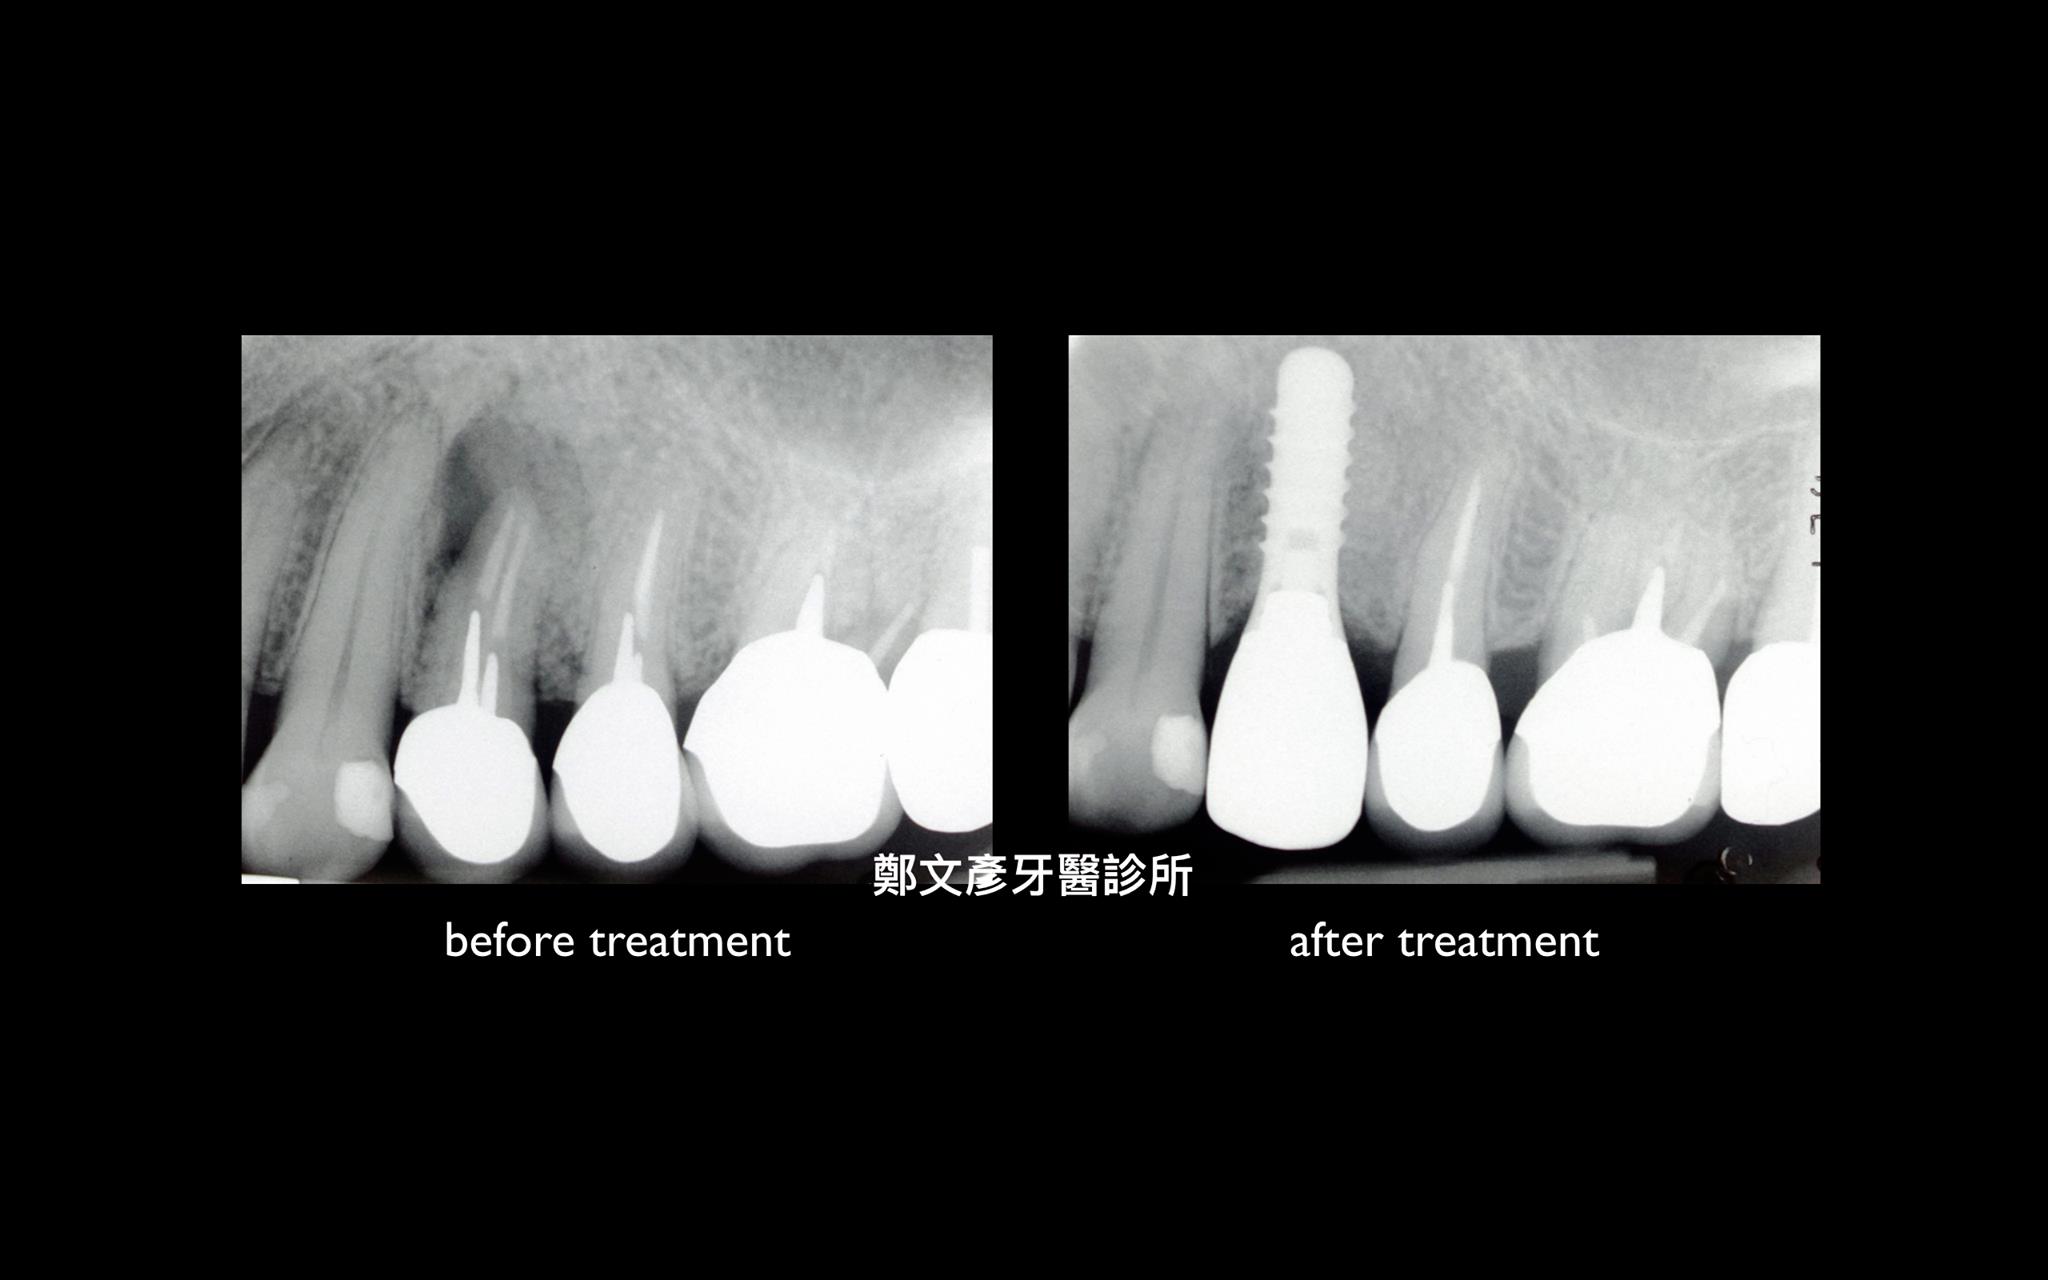

3. Role of granulation tissue in socket preservation

Role of granulation tissue in socket preservation